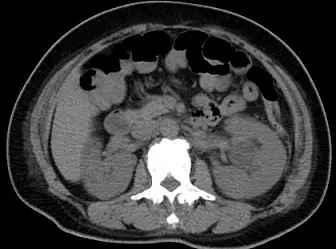

電腦斷層檢查如下圖,下列敘述何者最適當?

Aunenhanced abdomen CT

Bunenhanced pelvis CT

Cenhanced abdomen CT

Denhanced pelvis CT

- 影像中央後方可見腰椎(Lumbar vertebra)。

- 脊椎兩側可見呈現蠶豆狀的實質器官,即為雙側腎臟(Kidneys)。

- 影像左側(即病患右側)前方可見**肝臟(Liver)**下緣組織。

- 影像前方有許多含有空氣與糞便的腸道(Bowel loops)。

- 綜合以上器官位置(肝、腎、腰椎),此切面無疑屬於腹部(Abdomen),。若為骨盆腔(Pelvis),則應見到骨盆骨骼(如腸骨、薦骨)、膀胱(Bladder)、直腸(Rectum)及生殖器官等構造。

- 觀察脊椎前方的腹主動脈(Abdominal aorta)與下腔靜脈(IVC),其 CT 密度(HU值)與旁邊的背肌軟組織相近,並未呈現明亮的亮白色(高密度)。

- 觀察**腎臟(Kidneys)與肝臟(Liver)**實質,並未出現因對比劑灌流而產生的皮質/髓質分化(corticomedullary differentiation)或顯影,腎盂等集尿系統也沒有對比劑排泄的亮白顯影。